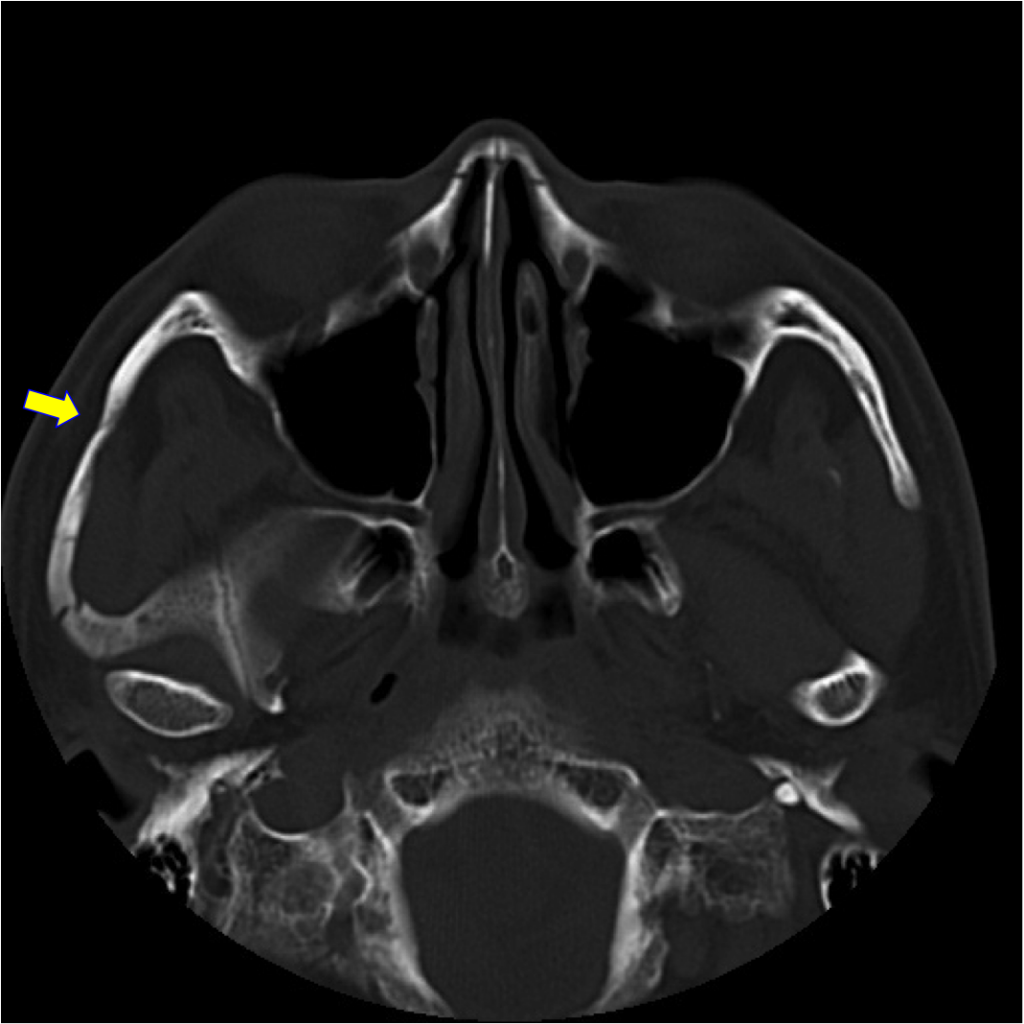

術前1(左)、2(右)

頬の外側に強い衝撃を受けると、頬骨の外側の弓なりになっている部位が骨折することがあります(矢印)。これにより、口が開きにくくなります。